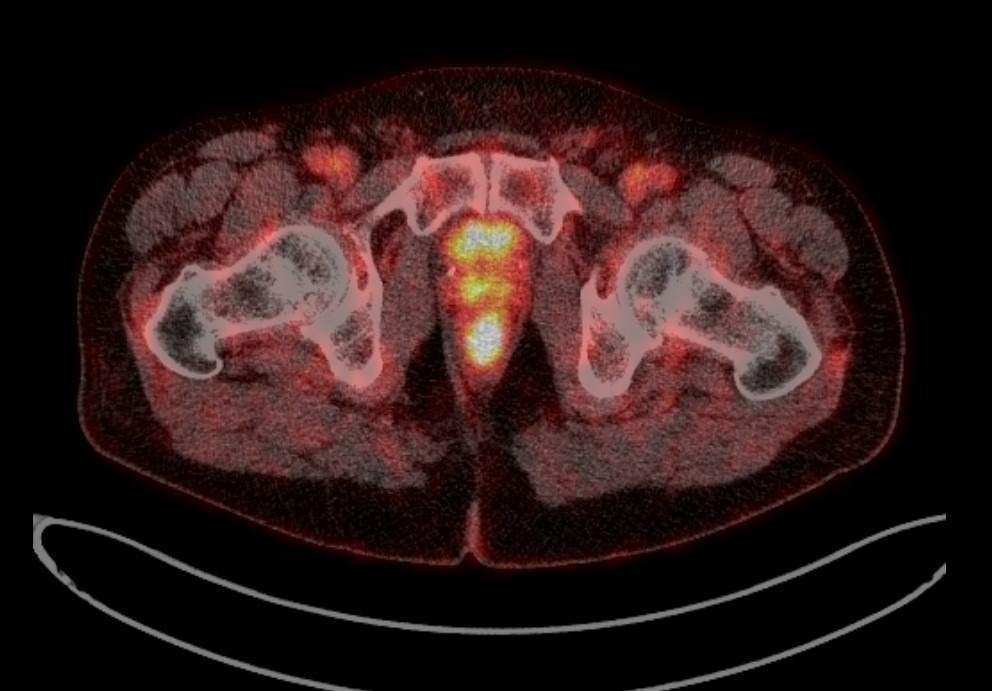

Рис. 7. ПЭТ-КТ изображение поражения предстательной железы у больного В.

Методом самой ранней диагностики возможного рецидива РПЖ является определение уровня ПСА, он же служит основанием к применению более дорогих и сложных способов диагностики (остеосцинтиграфия, МРТ, ПЭТ).

После облучения уровень ПСА должен понизиться, если сравнивать с исходным показателем. Большое значение для оценки эффективности терапии имеют динамика снижения и минимальный показатель. При этом нужно помнить, что определять уровень ПСА нужно каждый раз в одной и той же лаборатории, так как тест-системы имеют разную чувствительность, поэтому могут быть значимые расхождения в показателях, если забирать биоматериал у одного и того же пациента, но исследовать его в разных лабораториях.

Общепринятое определение рецидива после лечения – это повышение уровня ПСА на более чем 2 нг/мл относительно самого низкого его значения. Значение самого низкого уровня ПСА индивидуально и зависит во многом от исходных клинических показателей новообразования (степень злокачественности, локальная распространенность процесса).